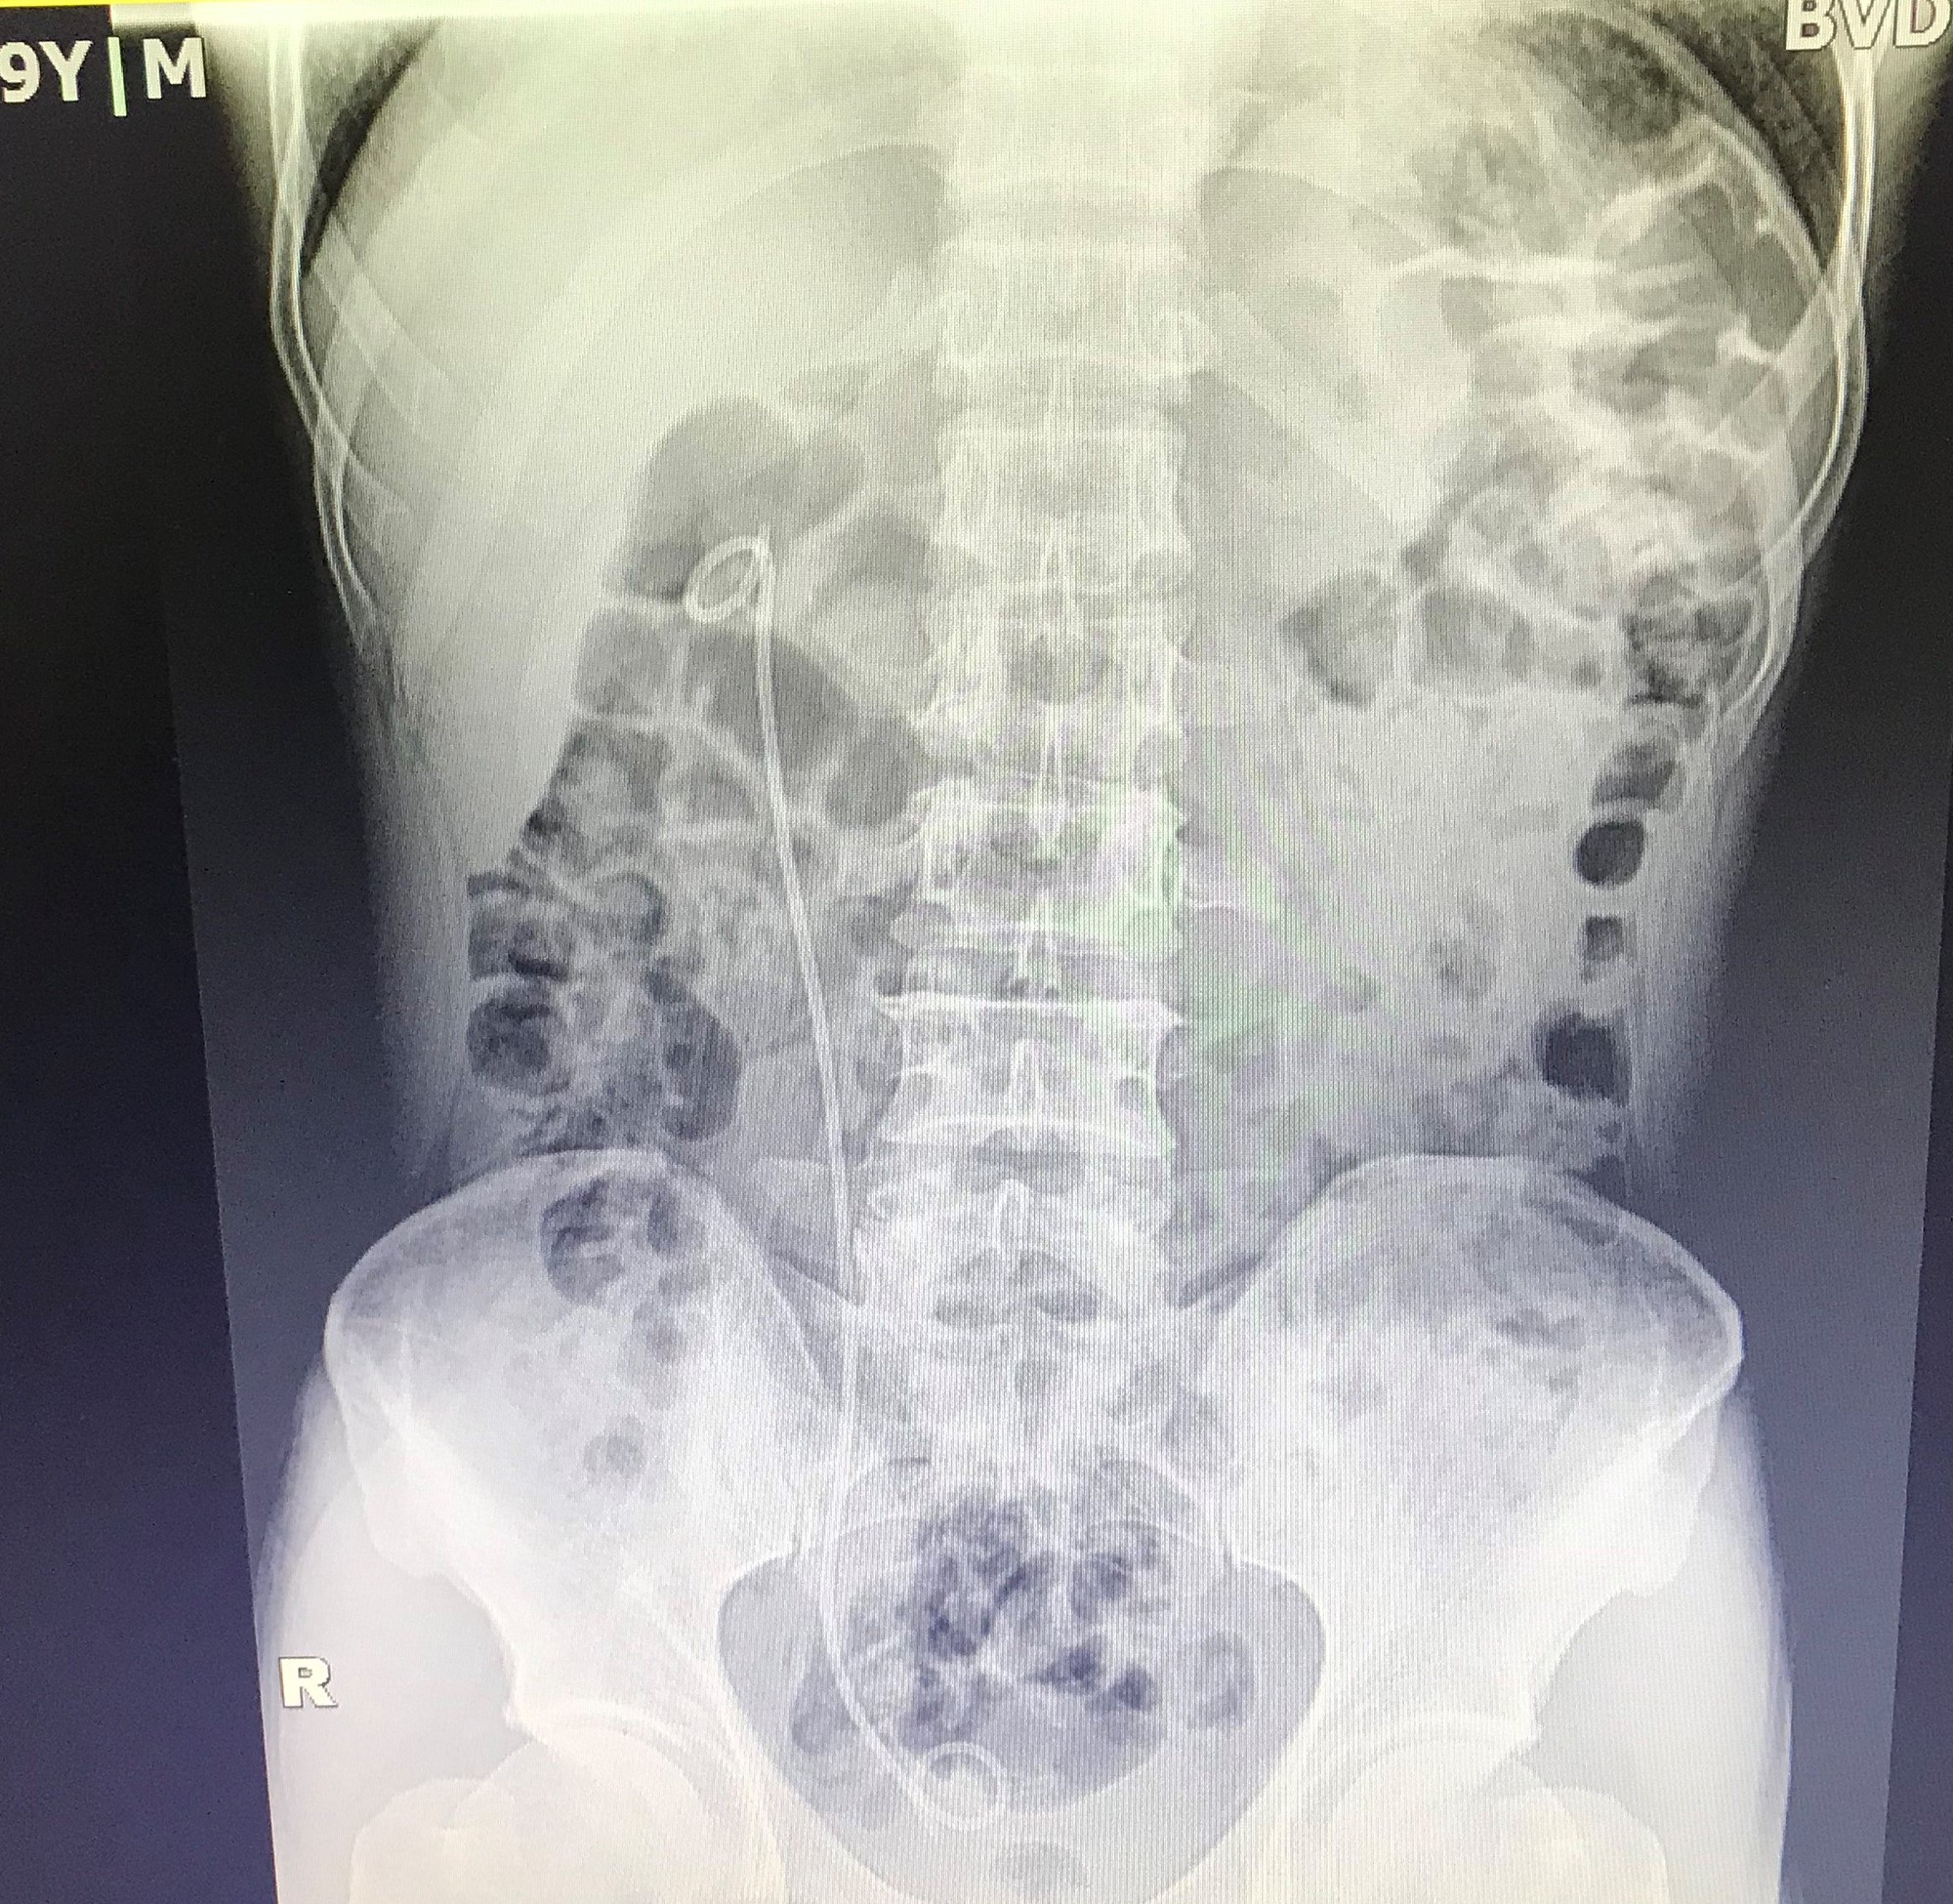

Bệnh nhân N.V.T, 58 tuổi, ở Cấp Tiến, Tiên Lãng, Hải Phòng có sỏi ở khúc nối bể thận – niệu quản phải kích thước 16x8mm gây ứ nước thận phải độ I, giãn đài bể thận phải, bệnh nhân có chỉ định tán sỏi ống mềm bằng laser. Ca phẫu thuật được TS.BSNT Phạm Việt Hà – Giám đốc chuyên môn, Trưởng Khoa Ngoại thận Tiết niệu – Nam học, Bệnh viện đa khoa Quốc tế Hải Phòng trực tiếp thực hiện. Chỉ trong vòng 30 phút, sỏi đã được tán vụn hoàn toàn và sau đó các mảnh sỏi được đưa ra ngoài qua đường bài xuất nước tiểu. Bệnh nhân gần như rất ít đau, có thể đi lại, tự chủ vệ sinh cá nhân ngay trong ngày đầu sau phẫu thuật.

Tán sỏi ống mềm là kỹ thuật được thực hiện bằng việc đưa ống soi mềm ngược dòng qua đường tiểu lên niệu quản – bể thận, vào các đài thận để tìm sỏi, tiếp cận trực tiếp viên sỏi và tán vụn sỏi bằng laser. Được đánh giá là kỹ thuật cao, chuyên sâu chỉ định cho bệnh lý sỏi thận, sỏi đường tiết niệu với kích cỡ sỏi nhỏ từ 10mm – 30mm ở các vị trí: sỏi 1/3 trên niệu quản, sỏi nhóm đài dưới song cổ đài phải rộng, sỏi nhóm đài trên, sỏi ở bể thận. Với kỹ thuật này, bác sĩ dùng ống mềm đi từ niệu đạo vào niệu quản và ngược dòng lên bể thận, góc quan sát rộng lên tới 360 độ kết hợp với năng lượng Laser mạnh nên gần như những sỏi với kích thước 10-30mm được phá hủy, tán vụn hoàn toàn.